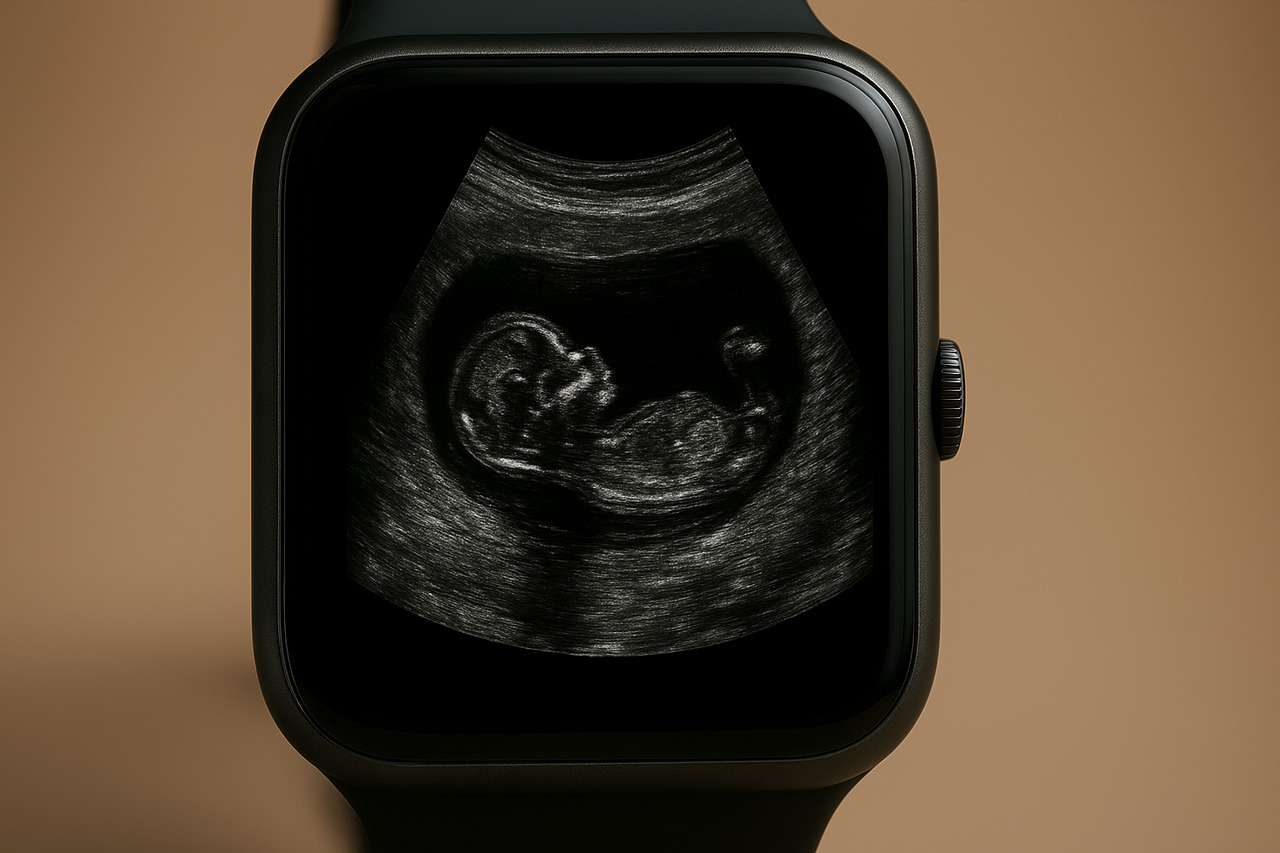

New Apple AI Detects Pregnancy With 92% Accuracy By Cross-Referencing Apple Watch Data With Sleep, Movement, And Body Signals

A new artificial intelligence developed by Apple has achieved 92% accuracy in pregnancy detection. The technology combines behavioral data, such as sleep and movement, with physiological signals collected by the Apple Watch. This approach has outperformed traditional methods that rely solely on biosignals.

The AI has been named WBM, short for Wearable Behavior Model. It analyzes data collected by devices like the Apple Watch and iPhone. Based on this cross-referencing, the system identifies changes in the body more efficiently.

Apple trained the model using over 2.5 billion hours of data from the Apple Heart and Movement Study.

Among the data used are step counts, heart rate rhythm, sleep duration, and movement patterns.

The analysis of these behaviors, combined with physical indicators, has increased the ability to predict not only pregnancy but also issues such as sleep disturbances, infections, and cardiovascular conditions.

The technology’s differentiator lies in the hybrid architecture of the system. WBM combines behavior analysis strategies with physiological information, allowing for real-time and more accurate monitoring.

The AI can detect rapid changes in the body and provide results with greater confidence.